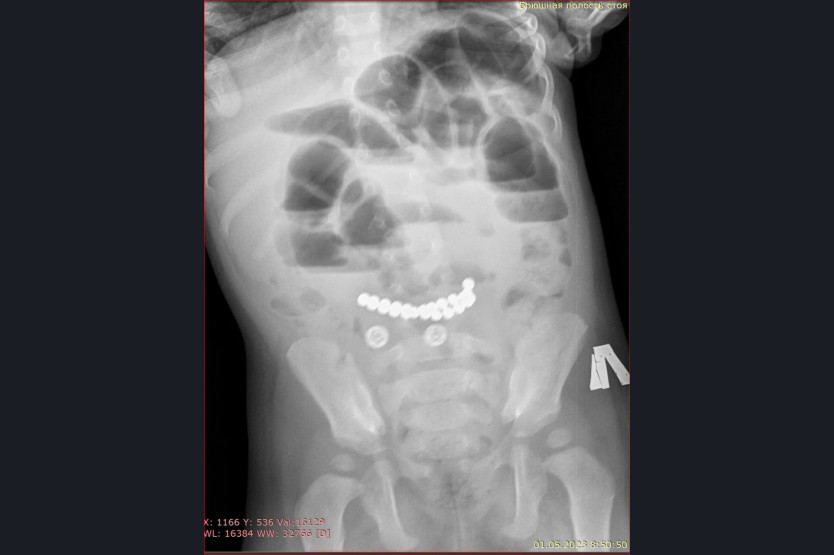

«Особую тревогу вызывают случаи, связанные с магнитами. ️Недавно в наше приемное отделение поступил ребенок с жалобами на многократную рвоту и сильные боли в животе. Обследование выявило множественные рентгенконтрастные предметы в кишечнике и явные признаки кишечной непроходимости. В ходе экстренной операции было удалено 25 магнитов», – рассказала главный врач ДГКБ № 1 Евгения Аверкина.

Магниты могут притягиваться друг к другу через стенки кишечника, это приводит к кишечной непроходимости, некрозу, перфорации кишечника и формированию свищей. К сожалению, длительное нахождение 25 магнитов в желудочно-кишечном тракте у этого пациента привело к серьезным осложнениям. Но сейчас жизни ребенка ничего не угрожает, операция прошла успешно.